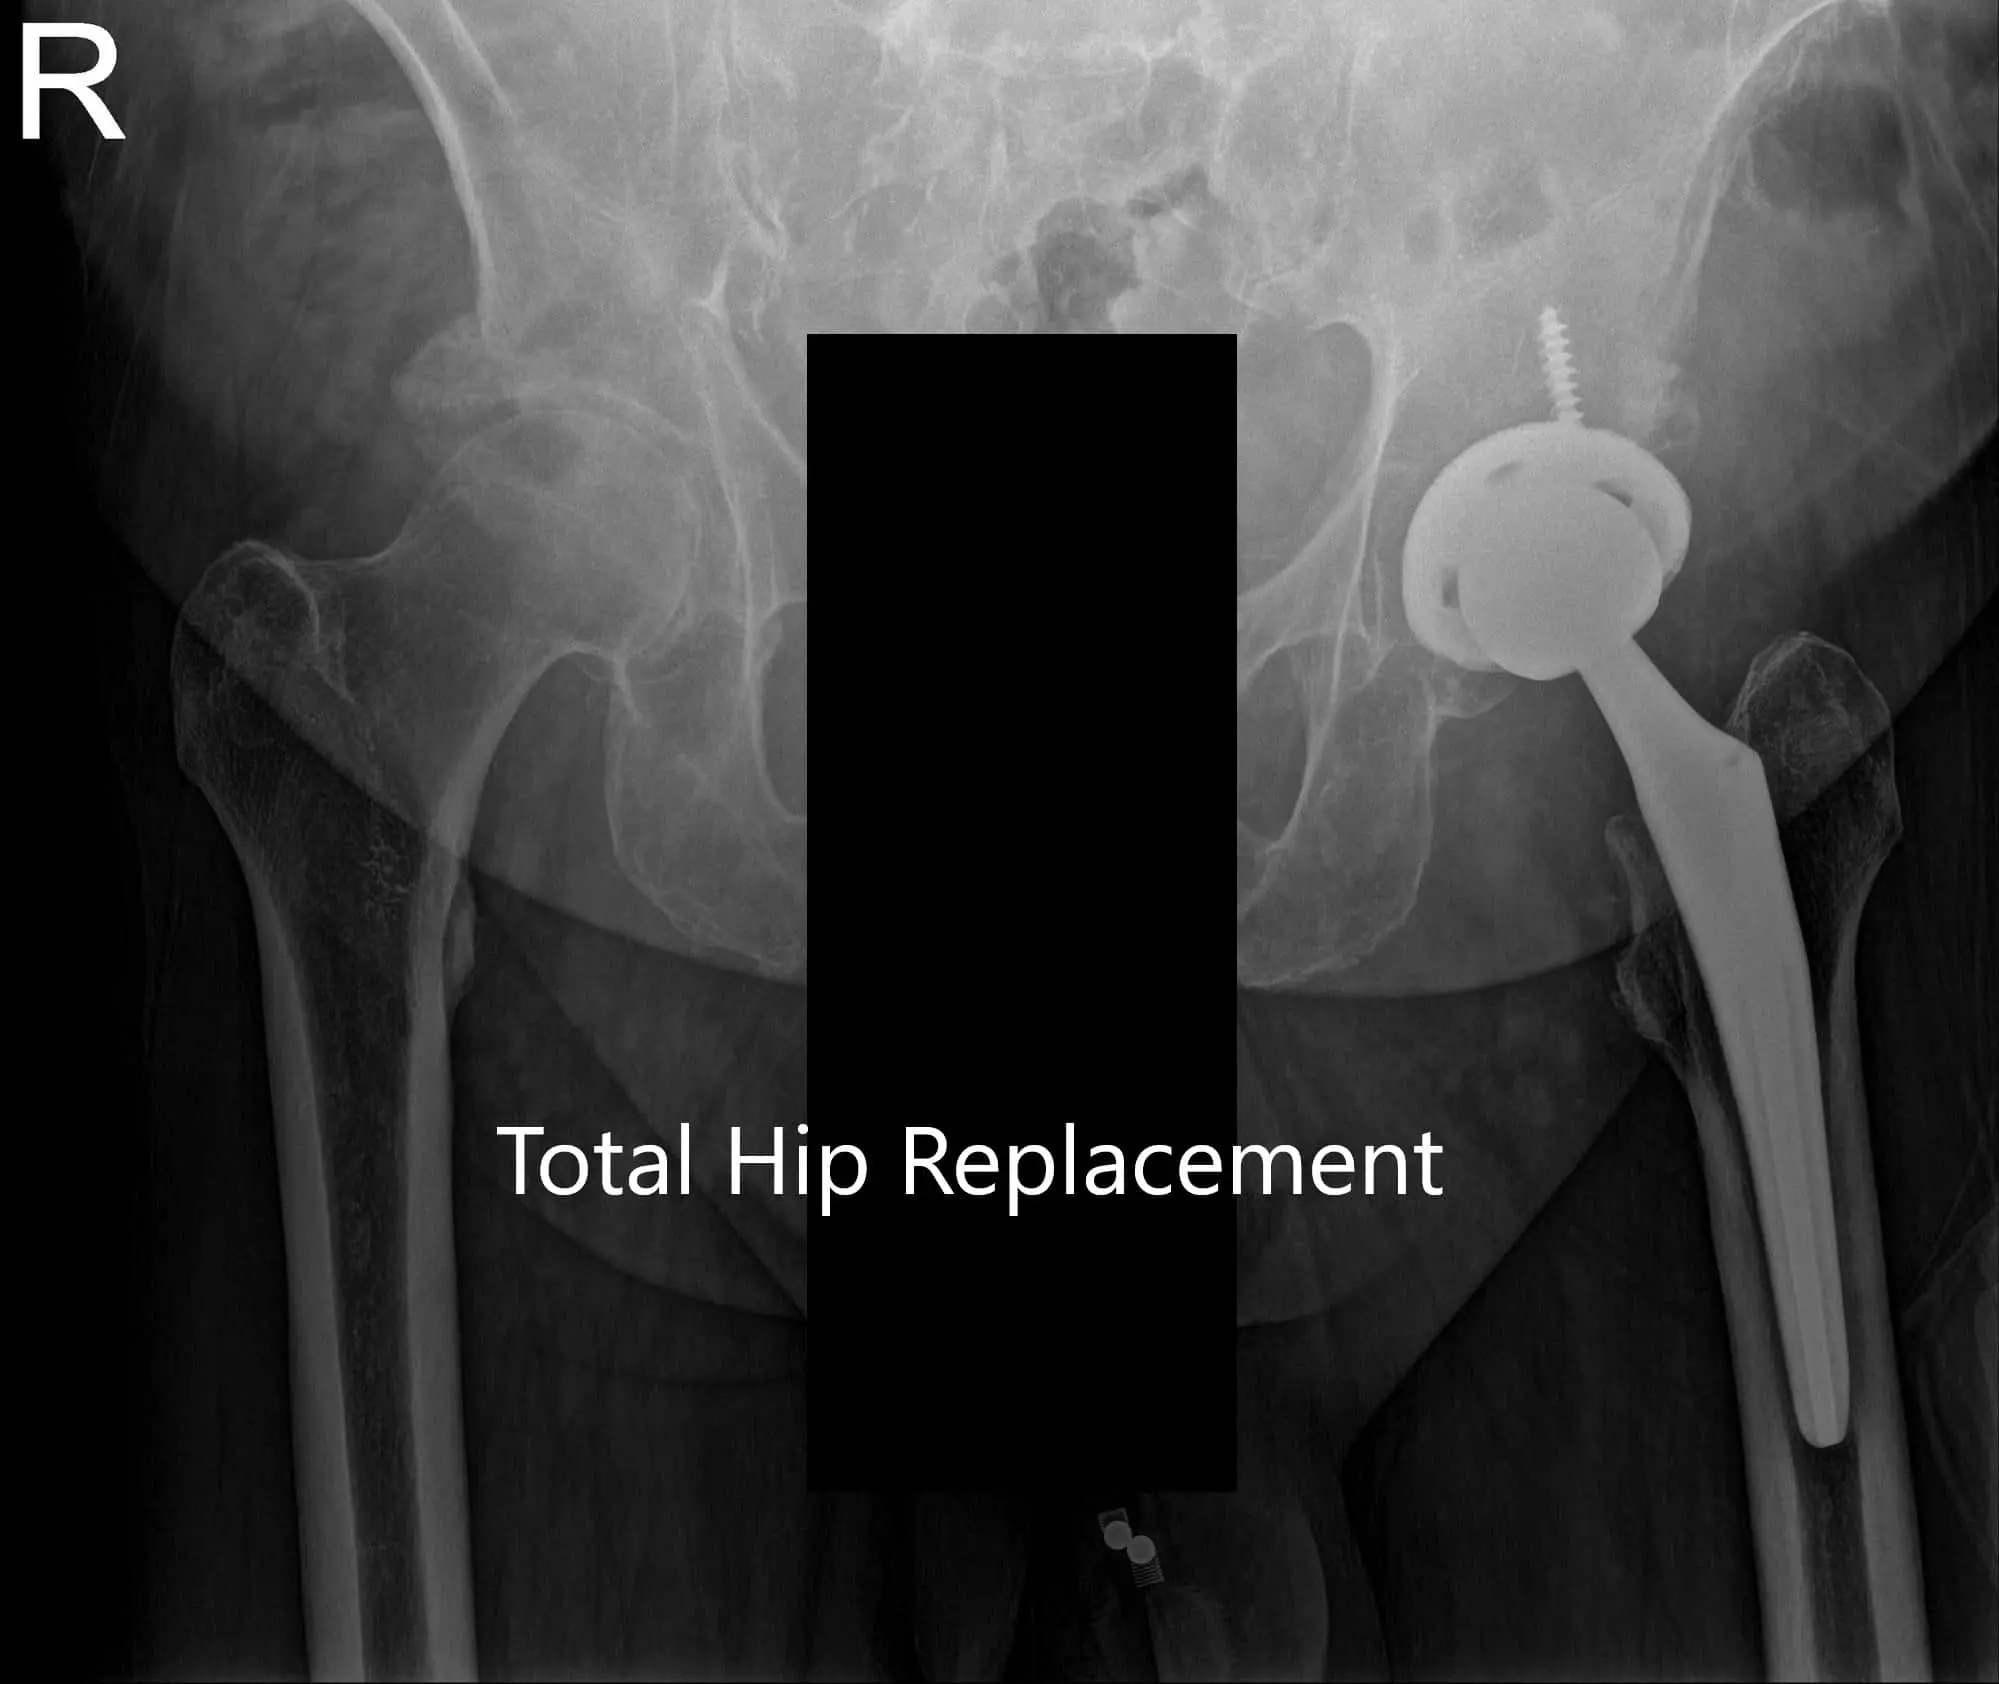

Postoperative X-ray of the Pelvis and lateral view of the left hip

Postoperative X-ray of the Pelvis and lateral view of the left hip - img 2

Postoperative X-ray of the Pelvis and lateral view of the left hip.